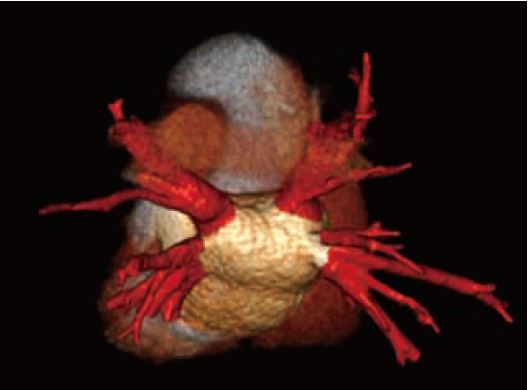

Наші типові пацієнти для обстеження КТА коронарних судин тепер отримують субмілізівертні дози опромінення з відмінною якістю зображення (рис. 8, 9). У молодих радіочутливих пацієнтів тепер ми можемо виконувати сканування значно нижче 0,5 мЗв, щоб відповісти на клінічне запитання (рис. 10). Таким прикладом є дослідження аномальних коронарних артерій, де справді все, що потрібно, — анатомічний огляд.

Рис.10 Попереднє планування абляції лівого передсердя. DLP 7 (0,1 мЗв)